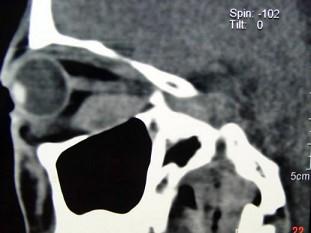

问题 男,52岁,双眼突出2-3年,请结合影像图像,选择最可能的诊断 ( )

选项 A、眼型Graves病 B、动静脉瘘合并眼外肌增粗 C、肌炎型炎性假瘤 D、眼肌发育异常 E、淋巴瘤

答案 A